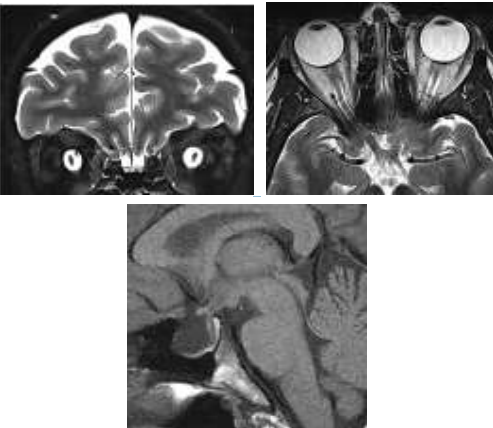

Paciente do sexo feminino, 33 anos, obesa, apresentando queixa de turvação visual progressiva e cefaleia de difícil tratamento. Foi avaliada por oftalmologista que descreve edema de papila. Realizou RM de crânio com os achados abaixo.

Assinale a alternativa que corresponde ao provável diagnóstico para o caso acima